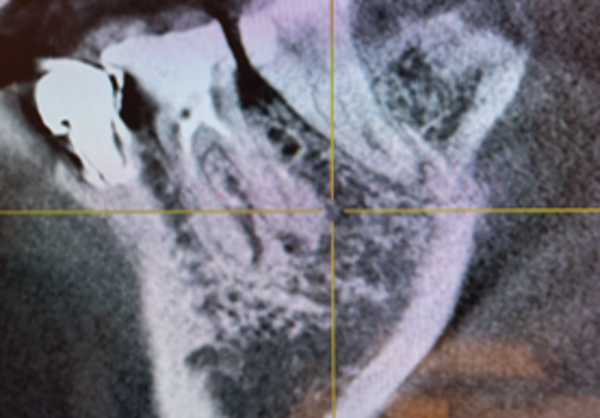

CTにて骨ができているのを確認し、被せ物を作製・装着しました。

併せて噛み合わせも細かく調整し、夜間の歯軋りのためのマウスピースも作製いたしました。

治療後の様子

もともと自覚症状はありませんでしたが、治療後は歯茎の炎症も改善し、歯周ポケットの測定値も良好です。